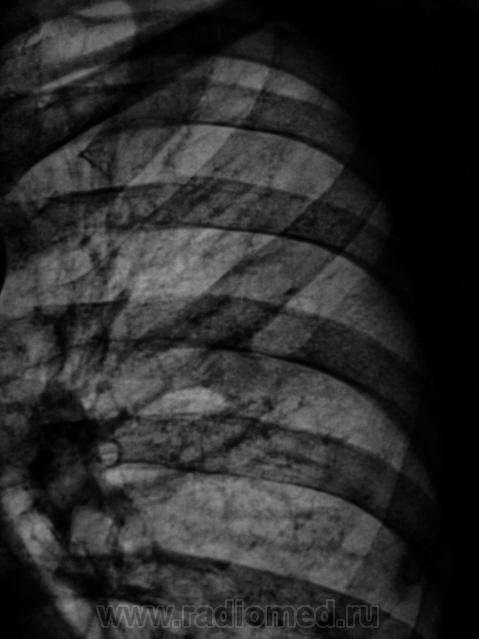

Вариант развития ребер слева.

"Шейное ребро".